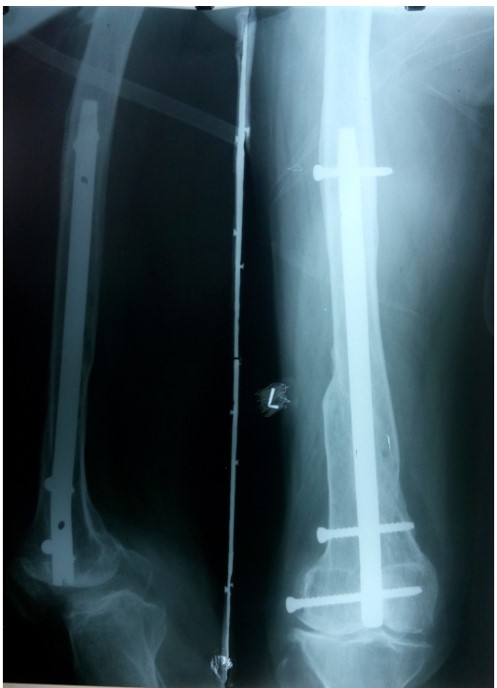

Femer

AVN